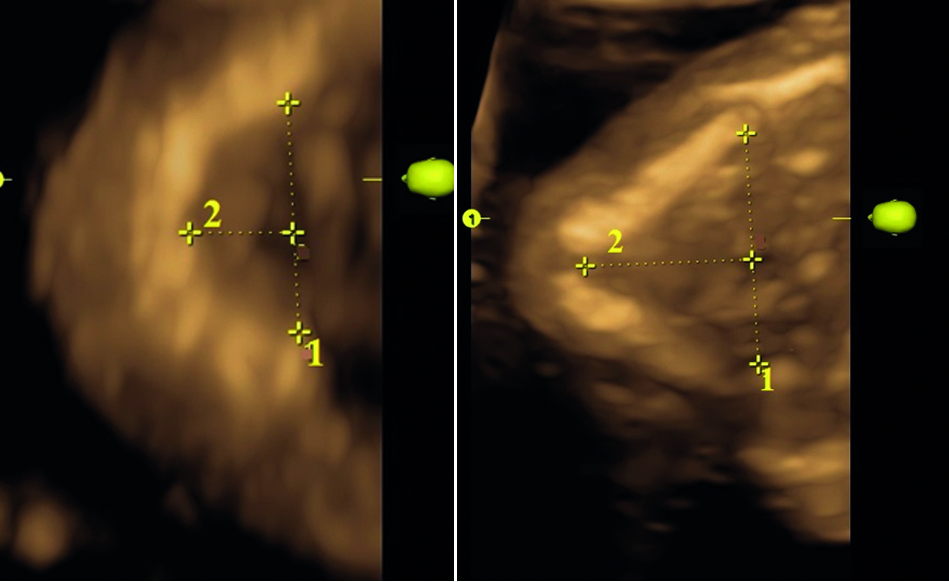

По форме тела нижней челюсти были выделены две группы: первая – широкие, короткие и вторая – длинные, узкие (рисунок 3). Их соотношение составило 2 к 1 соответственно (67% и 33%). В первой группе угловая ширина (фронтальный размер, расстояние между углами нижней челюсти) превышала проекционную длину (сагиттальный перпендикулярный размер между подбородочным выступом и серединой линии, соединяющей углы нижней челюсти) в 2 раза, во второй группе – в 0,3 раза. Широтно-продольный индекс (отношение угловой ширины к проекционной длине) был равен для каждой группы 90–94 и 155–164 соответственно.

Рисунок 3. Ультразвуковая сканнограмма нижней челюсти плода. А – Плод женского пола, 20 нед. Б – Плод женского пола, 19 нед. 1 – угловая ширина; 2 – проекционная длина.